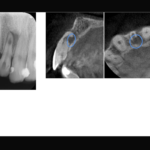

【約10 mmの根尖病変を非外科的根管治療で治癒した症例】「歯茎を押すと膿が出て痛い、他院で半年間治療するも治癒しない。」

- 約10 mmの根尖病変を非外科的根管治療で治癒した症例

- 治療内容: 上顎右側側切歯 根管治療(MTAを用いた根管充填)